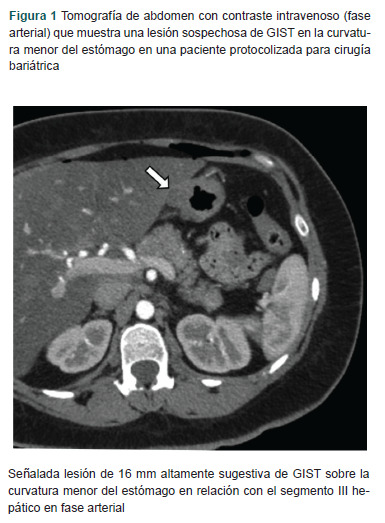

Clinical case: A 34-year-old female presented to the clinic for a gastric sleeve for obesity. Preoperatively, there was a GIST misdiagnosis. A CT scan showed a 16 mm gastric tumor in the lesser curvature adjacent to segment III of the liver. Endoscopic ultrasound showed a lesion arising from the muscularis mucosa. The biopsy was positive for spindle cells. The patient underwent a laparoscopic resection and Roux-en-Y gastric bypass. The pathology report showed S100-positive spindle cells compatible with gastric schwannoma.